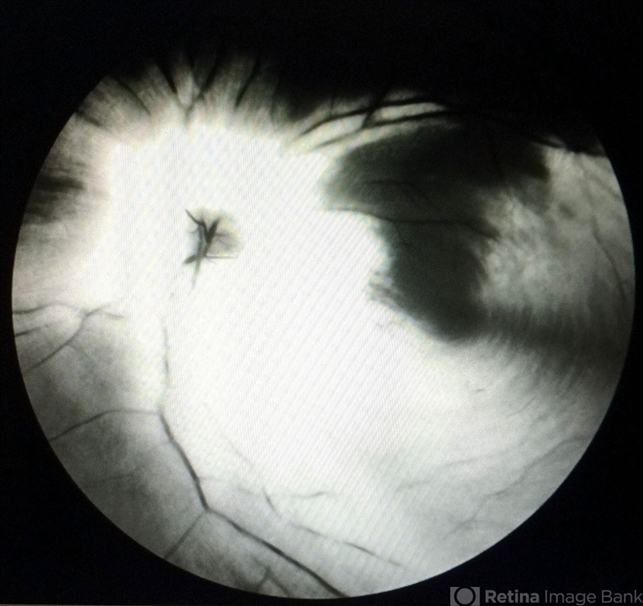

- myelinated nerve fibers

- Red free fundus photograph of the left eye of a patient with myelinated nerve fibre. Myelinated nerve fibres are autofluorescent and can be clearly made out on red free imaging